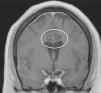

Materials and methodsEight paediatric patients met strict criteria for IND and were enrolled in this study. Electroencephalography (EEG), video electroencephalography (VEEG) and magnetic resonance imaging (MRI) were performed in all patients prior to surgery. Irreducible neuroagressive symptom was approached by lesional therapy based on most described targets for this disorder and assessed by the Overt Aggression Scale (OAS) pre-operatively and 6 months following surgery, using Wilcoxon test for statistical analysis.

Results and conclusionsThe average patient age was 13 years 2 months. 7 of the 8 patients enrolled had intellectual disabilities, 1 patient suffered neurologic sequelae referable to Dandy–Walker syndrome and 7 patients had no preoperative anatomical alterations. Following surgery, patients with IND noted improvement in their OAS. On average, the OAS improved by 39.29% (p=.0156), a figure similar in comparison to studies assessing treatment of IND in adult patients. The most satisfactory results were achieved in patients whose ablative therapy involved the Amygdala in their targets. There were no deaths or permanent neurological deficits attributable to procedure. To the author's knowledge, this is the largest series described in the literature for paediatric patients with IND treated with lesional stereotactic therapy.